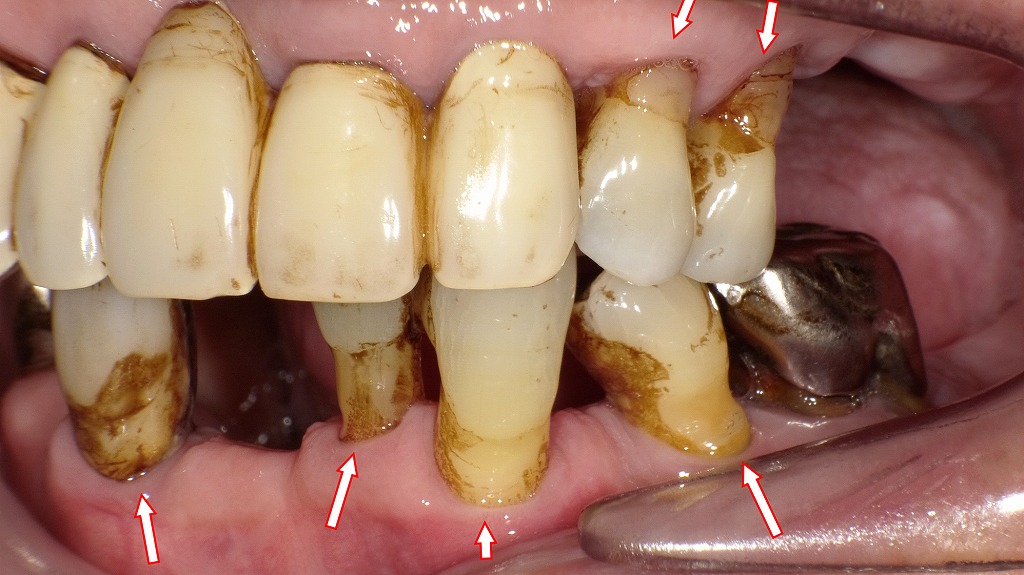

歯周病による歯肉退縮症例

この画像は、重度の歯周病や摩耗、着色が見られる口腔内の症例写真です。以下に詳しく解説します。

🦷 全体の特徴

- 歯全体に強い茶褐色の着色(ヤニ・コーヒー・茶渋などの外因性ステイン)が認められます。

- 歯肉の退縮により歯根面が露出しており、根面う蝕(歯根の虫歯)や知覚過敏のリスクが高い状態です。

- 右下6番には補綴物(クラウン・メタル修復)が見られ、長期使用によるマージン部の汚れや不適合が疑われます。

🔻 下顎(矢印で示された部位)

- 左下4番・3番・2番、右下1番:歯肉が著しく下がり、歯根が露出しています。

→ 長期的な歯周病進行または咬合性外傷の影響が考えられます。

→ ブラッシング時の刺激や咬合圧による歯肉退縮の可能性も。

🔺 上顎(矢印で示された部位)

- 左上4番・5番:歯肉退縮部にコンポジットレジン(CR)充填が行われています。

→ 歯根露出部の知覚過敏や審美改善のための処置です。 - 左上3番〜右上2番:保険の硬質レジン前装冠が装着されています。

→ 色調が黄変し、経年劣化により表面の艶が失われています。

→ 前装冠のマージン部(歯と冠の境目)に着色・プラーク沈着が認められます。

🩸 歯周状態の推察

- 歯肉の腫れは軽度ですが、**慢性的な歯周組織の破壊(歯槽骨吸収)**が進行している可能性があります。

- 歯間部や根面の清掃不良により、プラーク・歯石の沈着が広範囲に。

- 定期的な歯周治療(スケーリング・ルートプレーニング)とホームケアの改善が必要です。

💡 総評

この症例では、

- 歯周病による歯肉退縮

- 古い補綴物の劣化

- 全体的な着色と清掃不良

が重なっている状態です。

治療としては、歯周基本治療(スケーリング・ブラッシング指導)を行い、必要に応じて補綴の再製作や審美修復を検討する段階と考えられます。